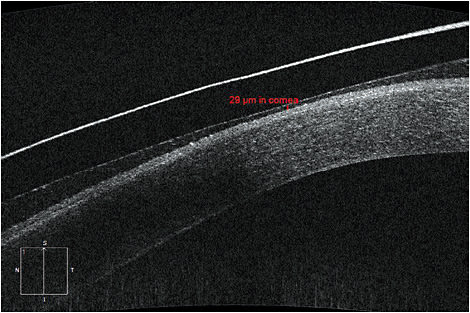

Careful biomicroscopy is mandatory when fitting scleral lenses, but minute findings can evade even the most astute clinicians. AS-OCT can clarify post-settling areas of concern. Lens clearances of 50 microns or less are difficult to observe behind the slit lamp and can be confused with lens touch (Figure 1). Lens awareness can also be difficult to solve (Figure 2). AS-OCT over uncomfortable areas in both primary and extreme gaze can identify whether edge lift, impingement, or poor lens design is to blame (Figure 3).